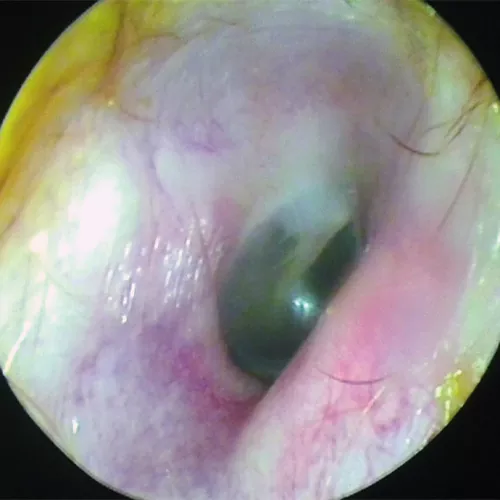

La otoscopia es la prueba fundamental para el diagnóstico, siendo definitiva en una parte importante de los casos. Existen muchas anomalías en la membrana timpánica asociadas a la otitis serosa. Por lo general, muestra un tímpano íntegro, edematizado y opaco con un aumento de la vascularización radial, y puede estar en posición normal, abombado o retraído. En los procesos de corta evolución la coloración suele ser rojiza, generalmente con una membrana engrosada. Sin embargo en los casos crónicos el aspecto suele ser azulado, resultado del depósito de hemosiderina en el exudado, y la membrana suele estar adelgazada y atrófica, con tendencia a la retracción, pudiendo desencadenar en una otitis adhesiva. En los casos en que el tímpano conserva su transparencia, es posible observar en ocasiones niveles o burbujas (indicativo de que la trompa funciona parcialmente).